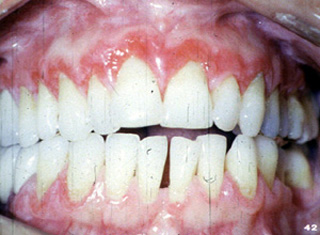

| A menudo

envuelve la encía y tiene una apariencia eritematosa y descamativa. Si

uno mira esta fotografía clínica, pueden verse áreas estriadas

blancas en la unión de la encía marginal con mucosa alveolar.

| Aquí hay

otra vista del eritema de la encía del liquen plano erosivo. |